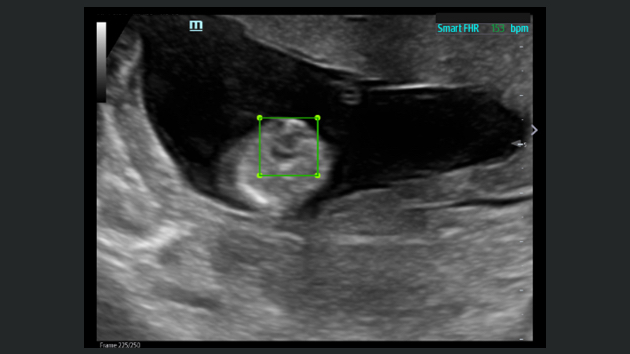

El sistema de ultrasonido TE9 estĂĄ dise?ado para ayudar a facilitar una mejor atenciĂłn al paciente y ampliar las capacidades de imagen para aplicaciones de anestesia, emergencias y cuidados crĂticos. Con funciones avanzadas, una gran pantalla tĂĄctil y una tecnologĂa de imagen superior, el TE9 es ideal para ayudar a mejorar la eficiencia clĂnica y la confianza en el diagnĂłstico. Las herramientas de automatizaciĂłn inteligentes brindan mediciones rĂĄpidas y reproducibles para exĂĄmenes y procedimientos fiables, incluso en entornos de gran presiĂłn.